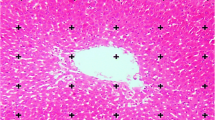

For histological studies, a piece of the liver was trimmed and fixed by immersion in Bouin’s fluid. The tissues were processed according to standard histological methods. Fibrosis was semiquantitatively assessed in 3-μm sections stained with hematoxylin/eosin or Sirius red, which mainly stains collagen fibers. The histopathological fibrosis scores were as follows: 0, no fibrosis; 1, perivenular and/or pericellular fibrosis; 2, septal fibrosis; 3, incomplete cirrhosis; and 4, complete cirrhosis [24]. The tissue slices were blindly scored by two expert pathologists. The degree of fibrosis was expressed as the mean of eight fields in each slide.

Specimens from the normal control group presented a normal structure. In specimens from the experimental group there was an apparent formation of fibrotic septa, encompassing regenerated hepatocytes into pseudo-lobules. Regenerated hepatocytes underwent severe lipoid degeneration. Specimens from the CCl4 + quercetin group showed only mild fibrogenesis without pseudo-lobule formation. Statistical analysis showed that fibrogenesis in the CCl4 + quercetin group was less severe than in the CCl4 group (Table 4).

CCl4-induced cirrhosis is considered a classic, replicable model used to study the different morphophysiological and histological aspects present in the complex structure of the human liver. A normal lobular structure was observed in the liver of control animals in the present study. The main structural modifications observed in the cirrhotic liver are those related to nodular disorganization, whose structure is characterized by fibrotic septa that cross the parenchyma or form variously sized nodules [47, 52]. In this work, when the animals received quercetin, little portal and periportal fibrosis was observed, with occasional portal-portal bridges, nevertheless without clearly outlining the formation of nodules, without the presence of steatosis, results which suggest an improvement of liver histology.